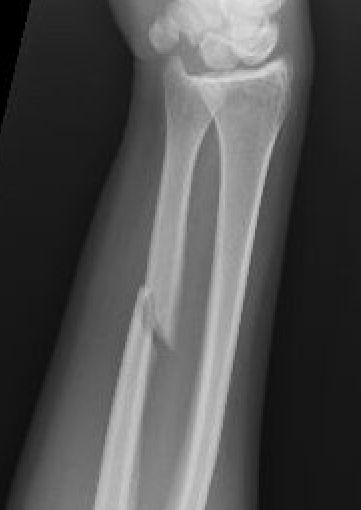

Nonoperative management

Indications

Minimally displaced fractures

- < 50% displaced

- < 10 degrees angulation

Increased nonunion rates with midshaft versus distal fractures

- increased nonunion with midshaft (30%) versus distal 1/3 fractures (2%)